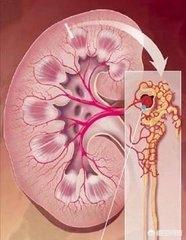

L'hypertension artérielle peut également entraîner une atrophie des reins.

Les reins normaux sont ronds et pleins, et l'hypertension artérielle à long terme entraîne un rétrécissement des reins des patients, avec une surface granuleuse et une diminution de la fonction rénale.

L'hypertension est généralement considérée comme une pression élevée à l'intérieur des vaisseaux sanguins, qui ne sont pas seulement ceux que nous mesurons dans nos bras, mais aussi tous les vaisseaux sanguins de l'ensemble du corps où la pression est élevée. La pression artérielle étant persistante, une pression artérielle élevée à chaque minute et à chaque seconde causera des dommages aux vaisseaux sanguins. Par exemple, nous entendons souvent parler de maladie coronarienne, d'infarctus cérébral, d'occlusion vasculaire des membres, de lésions rénales, de lésions vasculaires rétiniennes, qui peuvent être causés par l'hypertension. Dans le processus d'endommagement des organes cibles de l'hypertension, le rein est le premier organe à développer des lésions. Par conséquent, pour les patients hypertendus, l'évaluation des lésions rénales est très importante. Voyons cela de plus près.